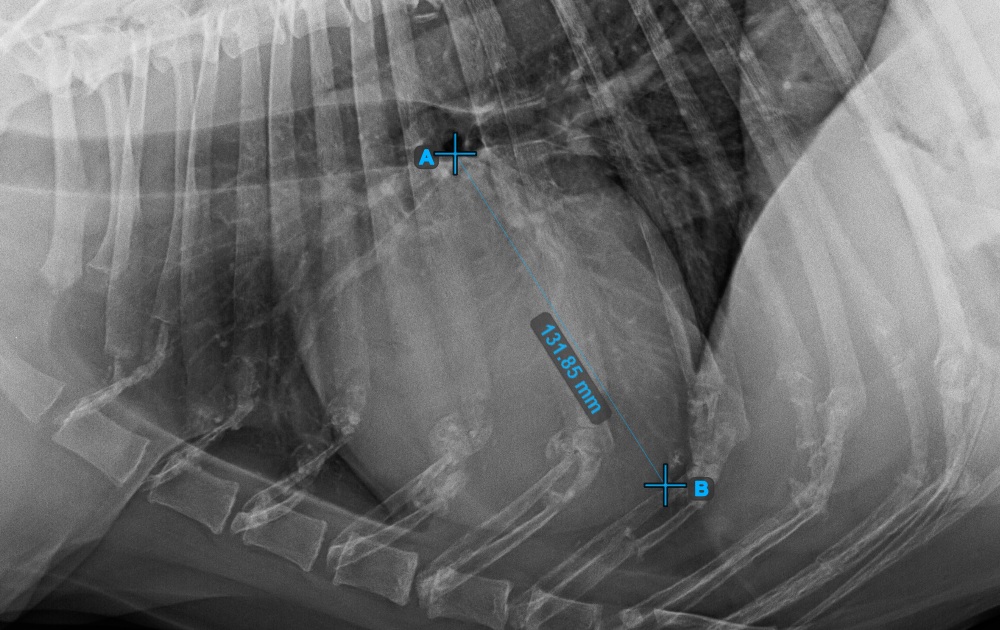

Indítsa el a mérést a Bifurcatio tracheae megjelölésével, a szív felső részéhez közel.

Az alábbi kép a Bifurcatio tracheae pont tipikus elhelyezkedését mutatja.